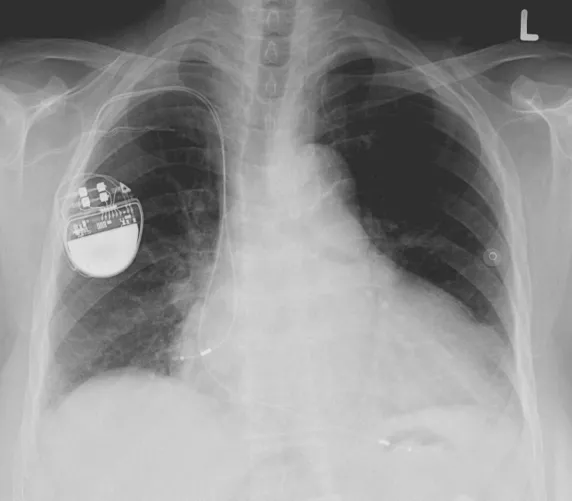

Beültetett pacemaker mellkasi röntgenfelvételen

Pacemaker röntgenfelvételen – szerző: Lucien Monfils, liszensz: CC BY-SA 3.0 (Wikimedia Commons)